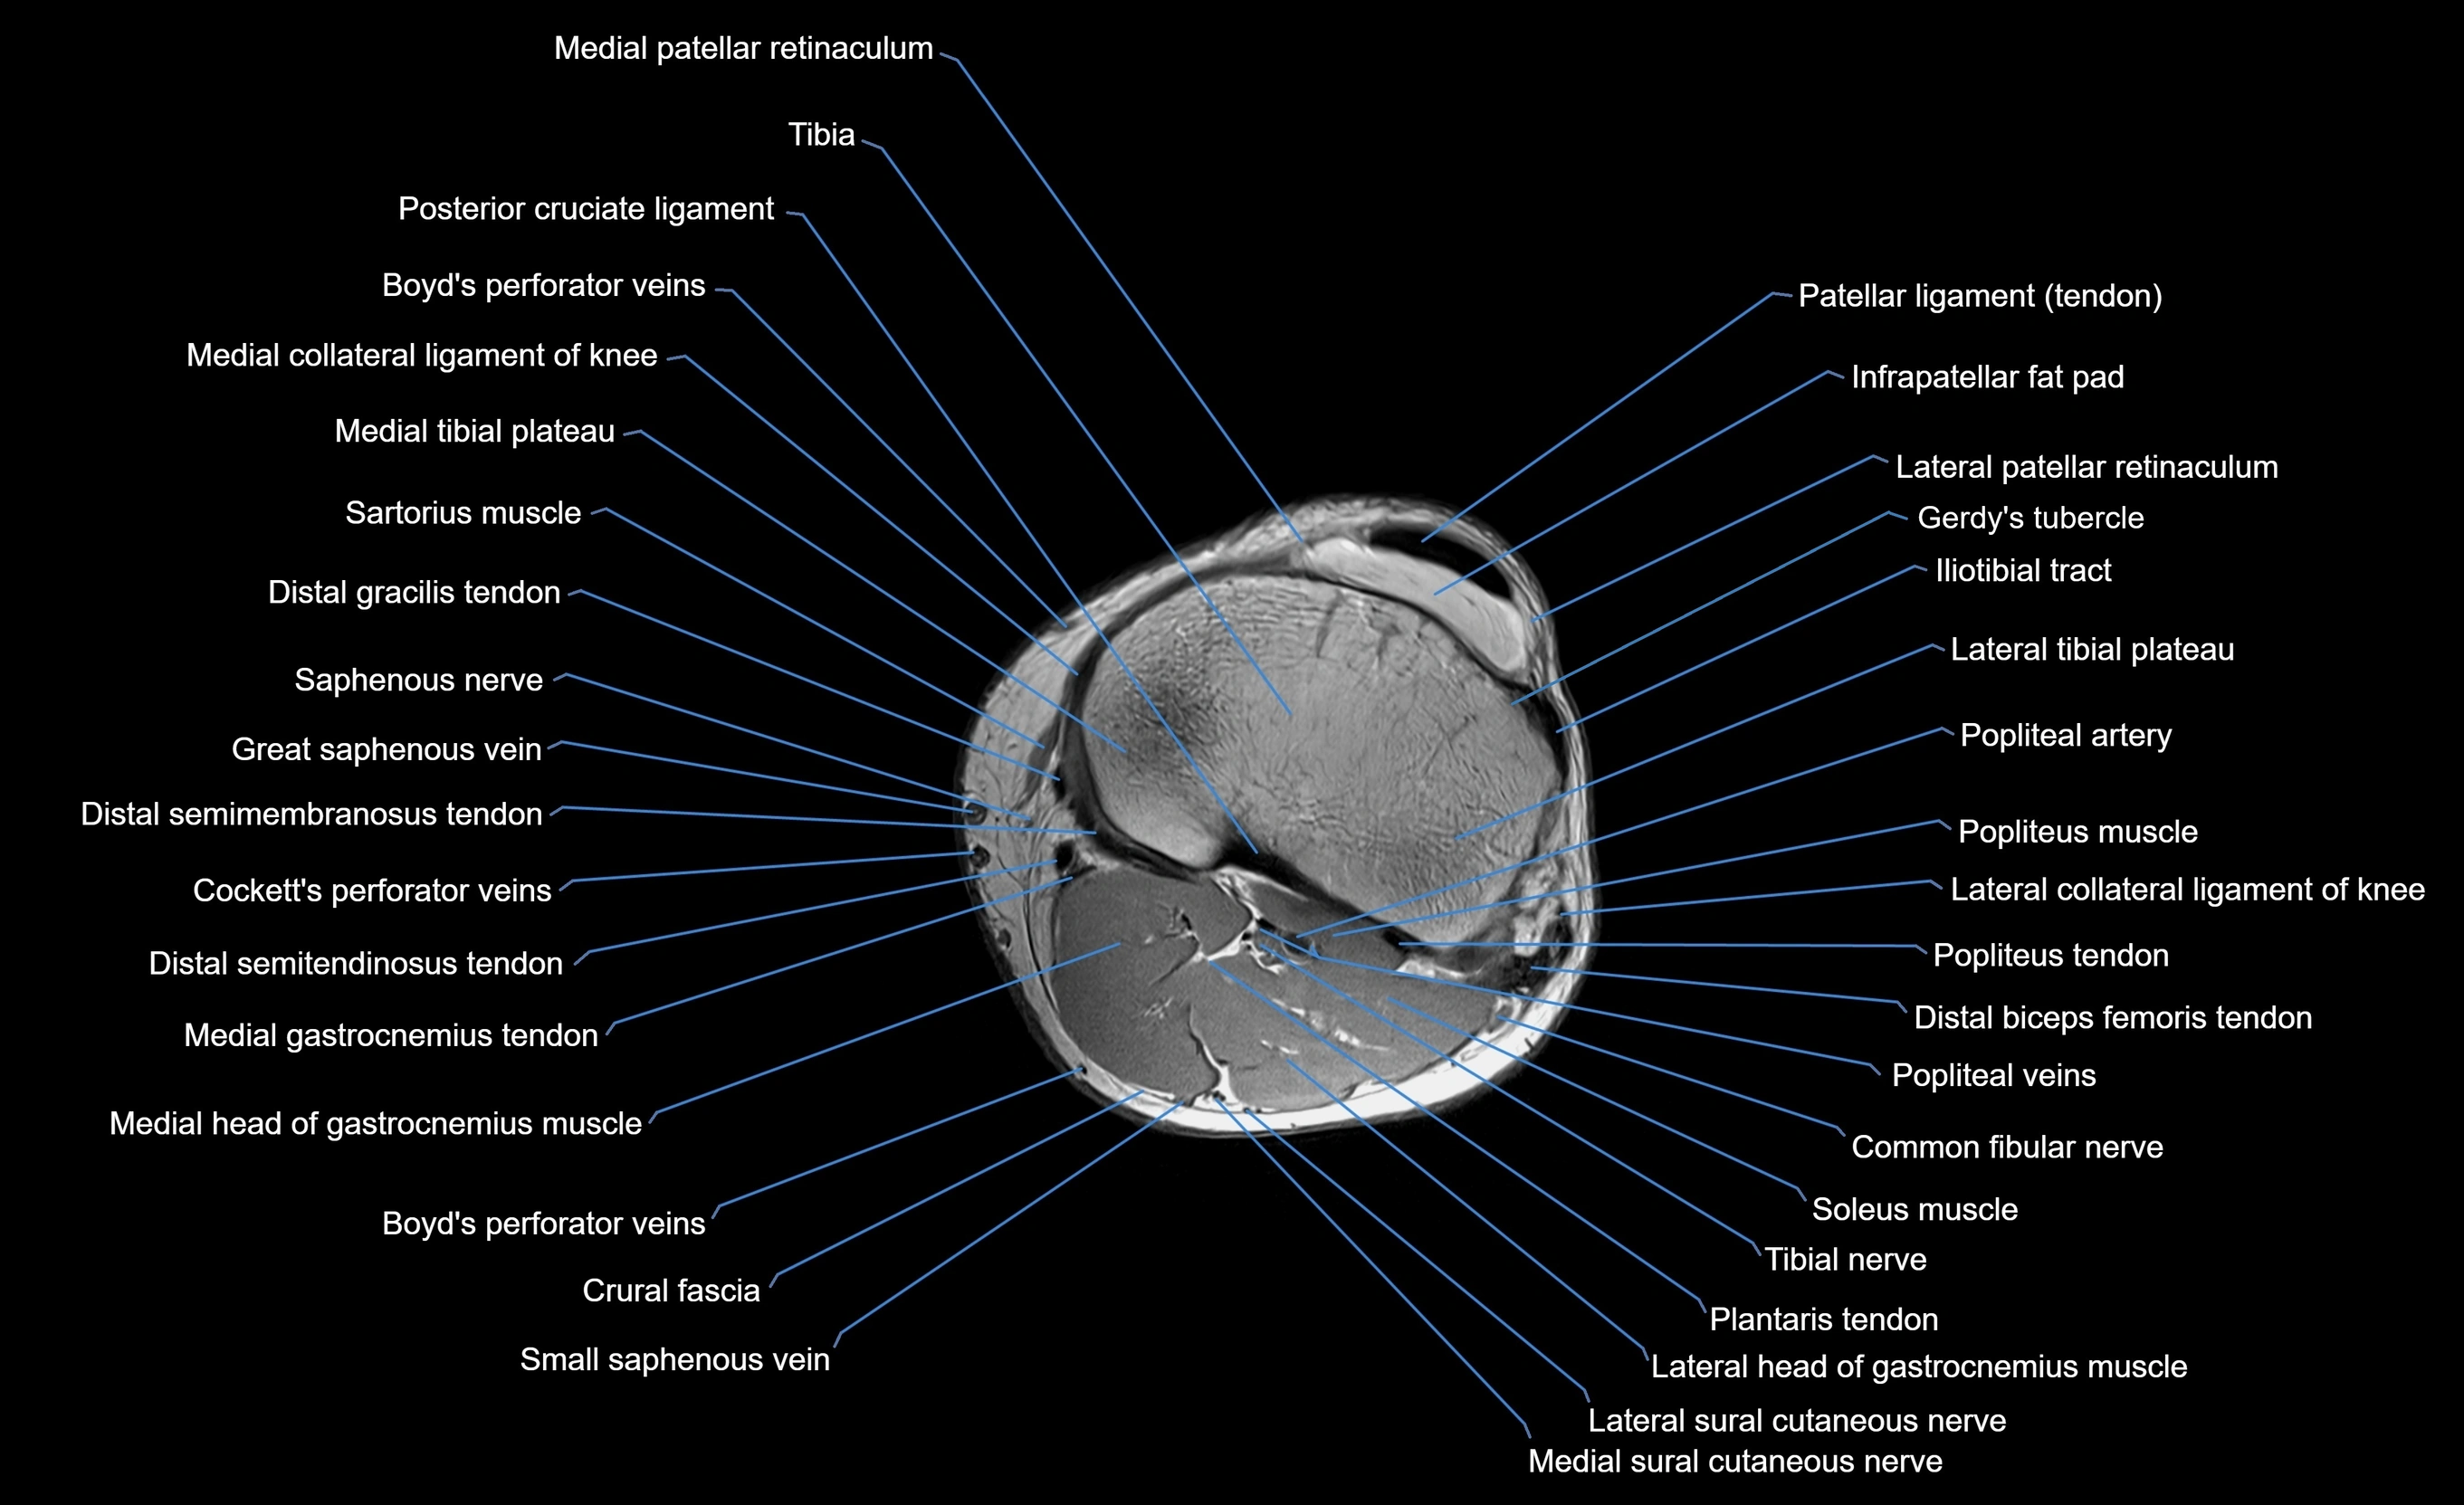

MRI image